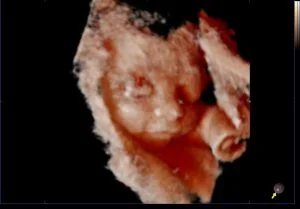

Como são as imagens vistas no exame?

Aqui está um exemplo de como será a visualização do bebê durante o exame: